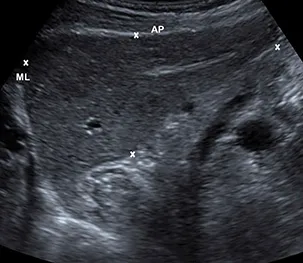

Liver size

Appearance

Measurements

Diameter | Female cm (mean ± SD) | Male cm (mean ± SD) |

Midclavicular line (largest craniocaudal diameter) | 14.9 ± 1.6 | 15.1 ± 1.5 |